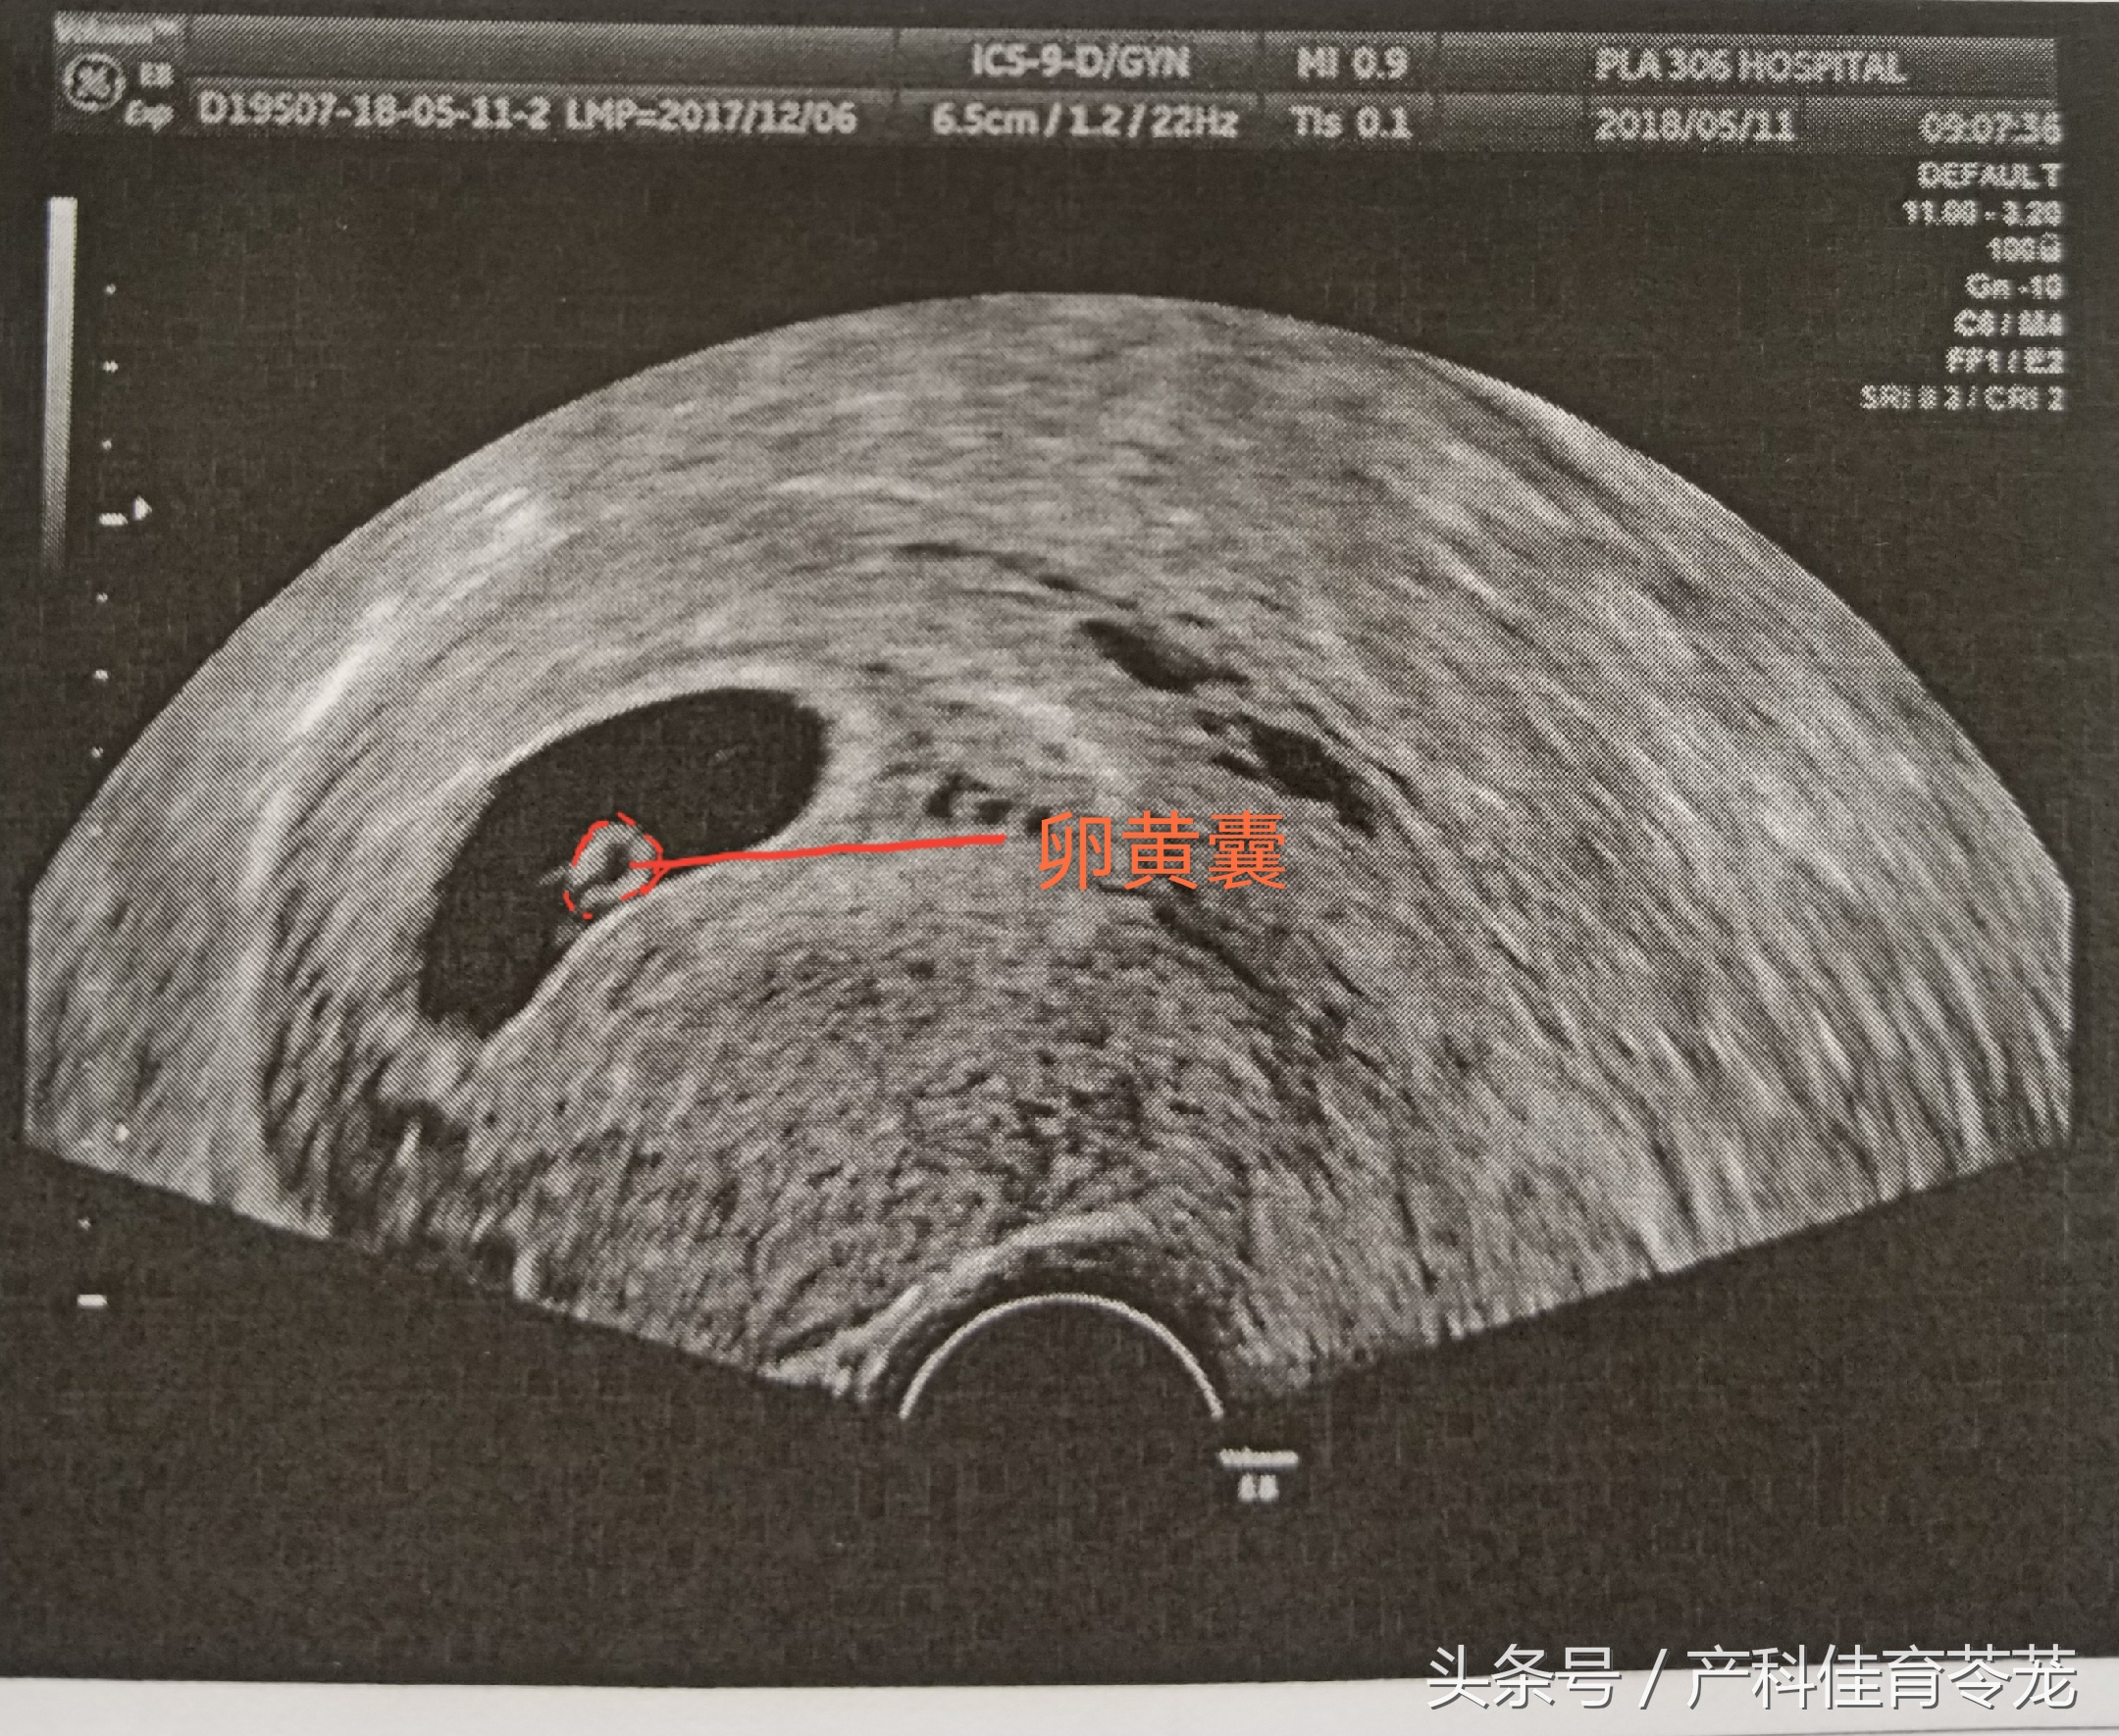

二、卵黄囊(Yolk Sac)

b超的3组数字代表什么,b超图片上的数字

卵黄囊是附着在胚胎上的膜囊,是妊娠囊内超声能看到的第一个解剖结构。